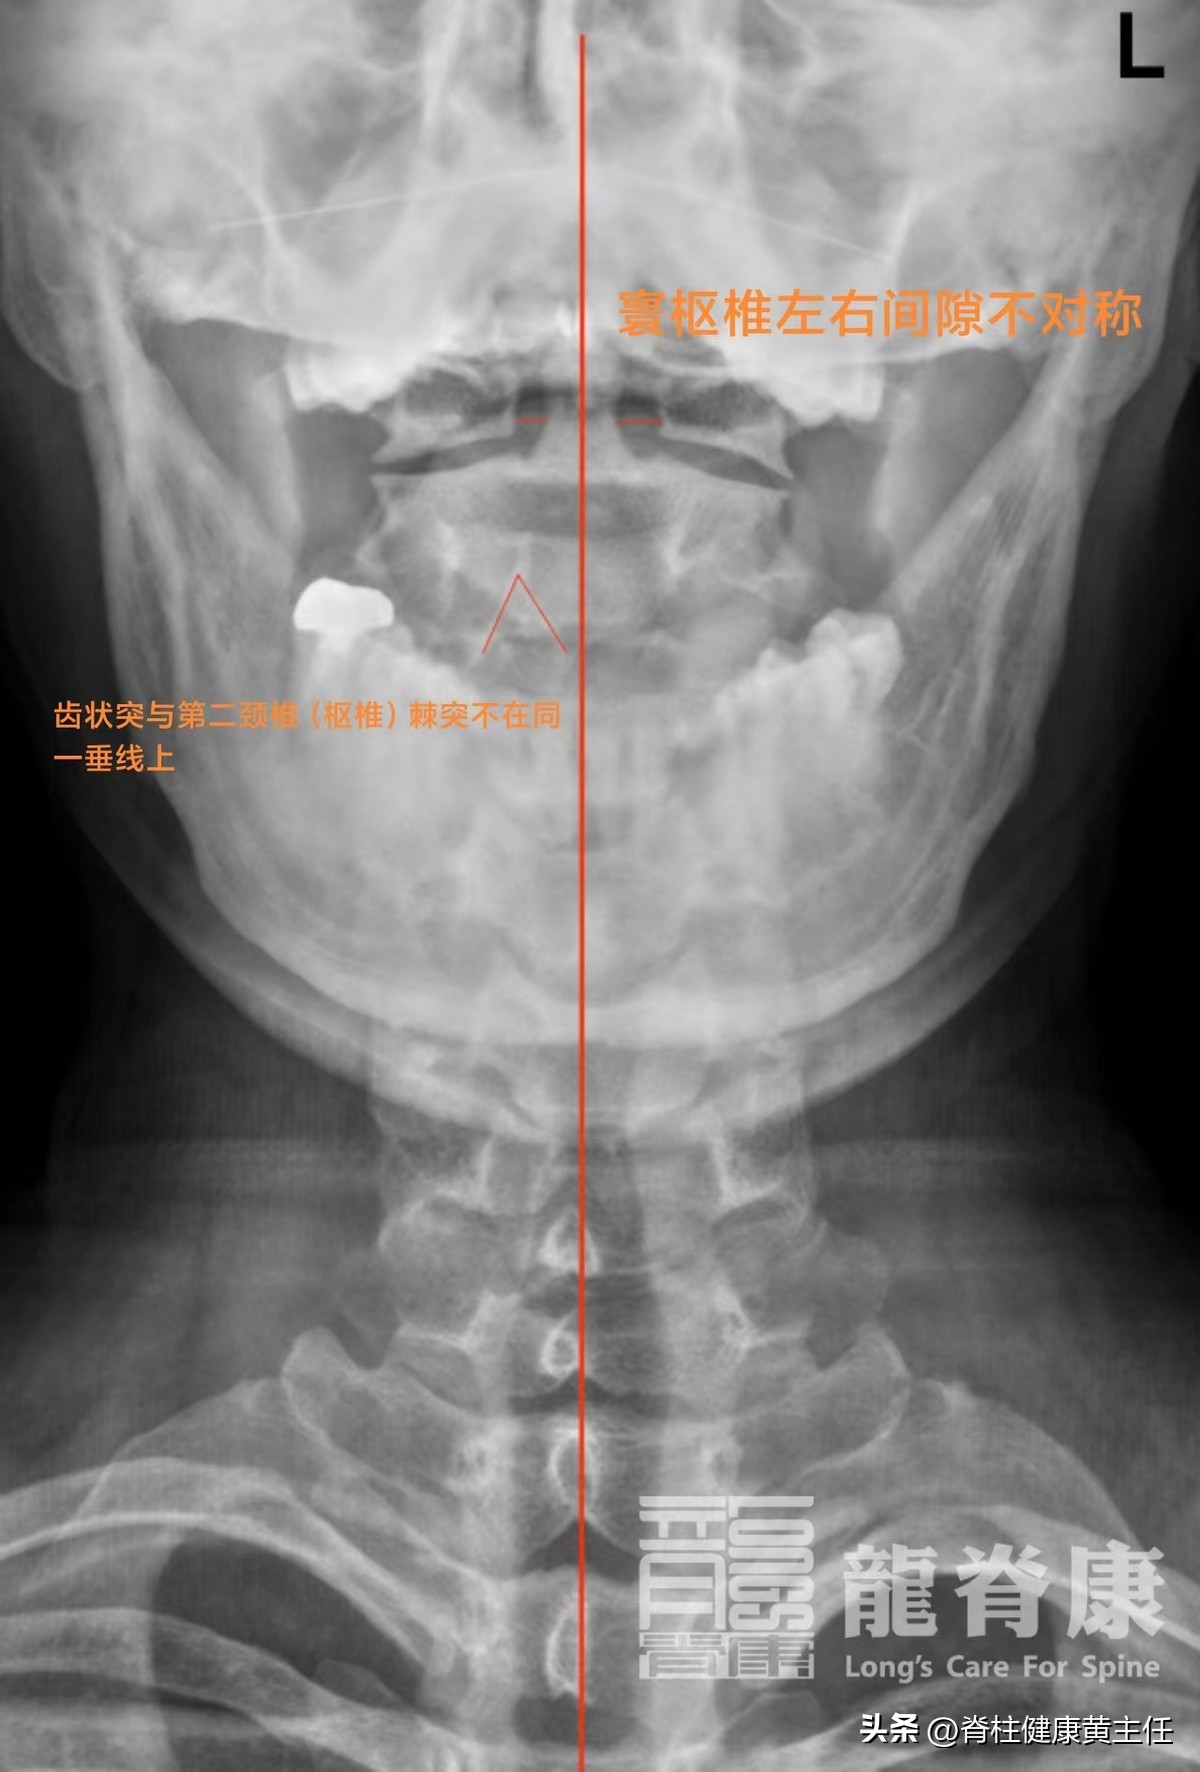

2021-03-31外院DR阅片示:颈椎退行性变、寰齿间隙不等宽,请结合临床、颈椎生理曲度变直。

诊断依据: 结合影像检查和体格检查,初步诊断是该患者颈椎退行性变、寰枢间隙左右不对称、有头晕、双侧手麻等症状,判断 颈椎小关节错位 卡压神经根、血管等,诱发不适症状,通过针对性的松解关节调整处理后,症状缓解。